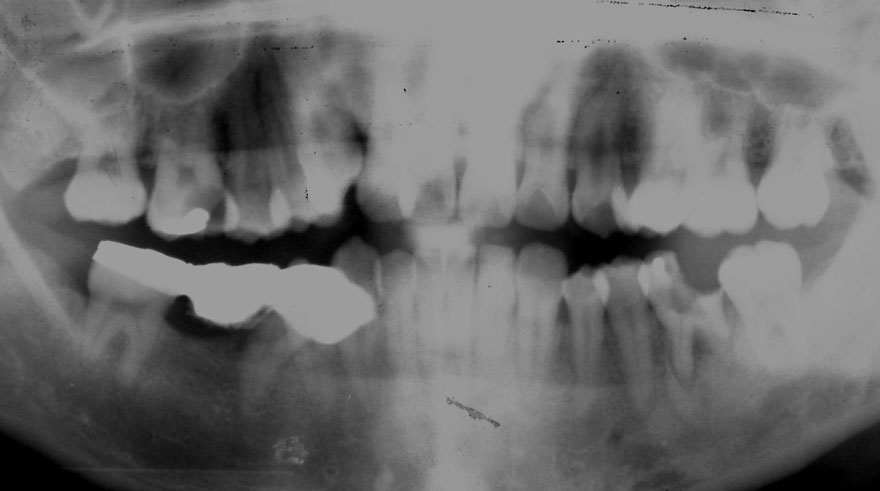

初診時 25歳 男性 平均歯槽骨喪失量:1.43mm

30年後 55歳

平均歯槽骨喪失量:1.56mm

22年間喪失量:-0.14mm

年間喪失速度:-0.005mm

(ケア頻度:4.21ヵ月ごと)